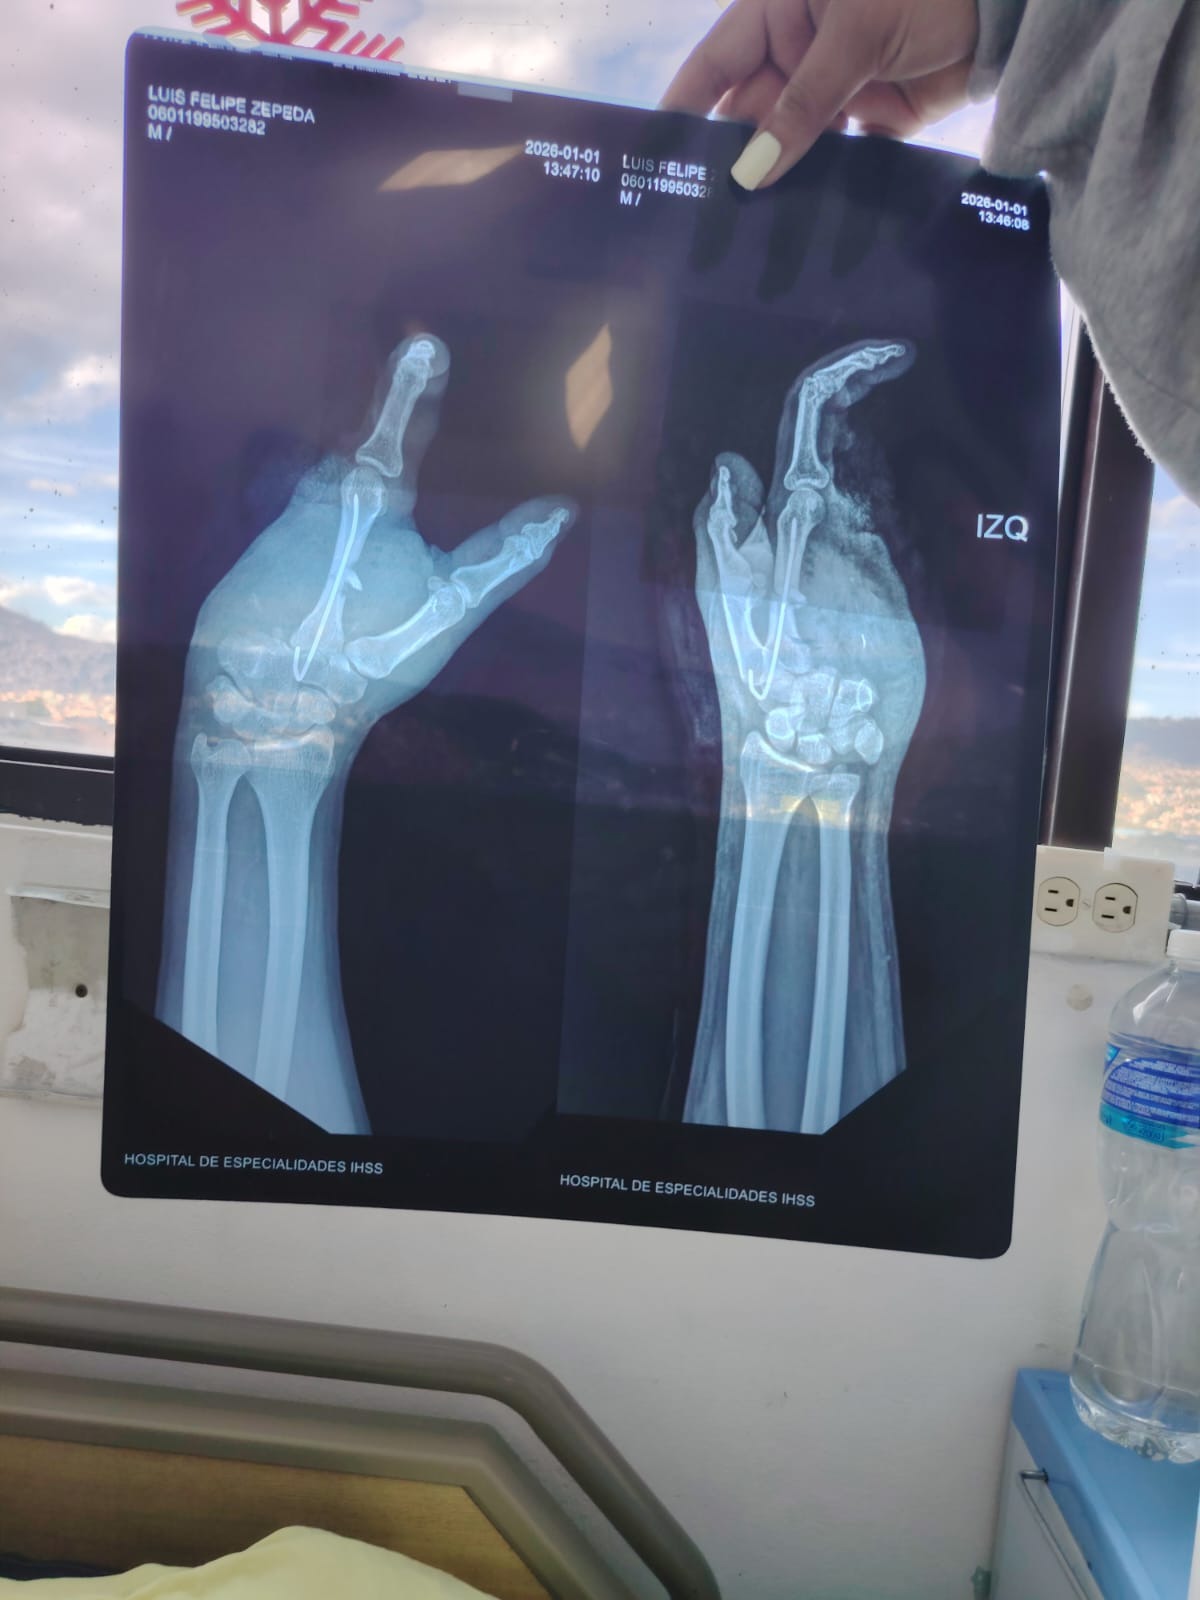

On New Year’s Eve, what should have been a night of celebration turned into a life-changing tragedy. Luis Felipe suffered a devastating fireworks accident that caused him to lose three fingers and part of the palm of his hand. He is only 30 years old, and in a matter of seconds, his life was completely altered.

En la víspera de Año Nuevo, lo que debía ser una noche de celebración se convirtió en una tragedia que cambió su vida para siempre. Luis Felipe sufrió un devastador accidente con pólvora que le causó la pérdida de tres dedos y parte de la palma de su mano. Tiene solo 30 años y, en cuestión de segundos, su vida cambió por completo.